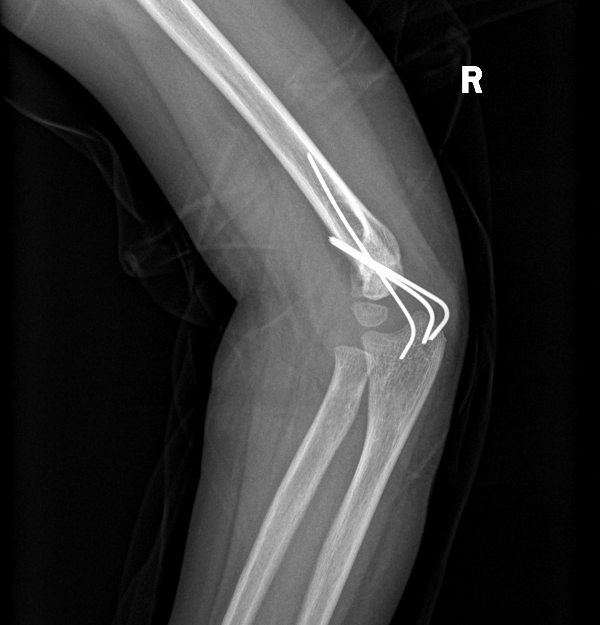

家长坚持不手术胳膊摔骨折五岁男孩胳膊肘 向外拐

儿童肱骨髁上骨折 父母需要知道的事情 肱骨骨折 手术

家长讳疾忌医导致孩子手臂畸形 现在后悔莫及 知乎

父母揪心的儿童肘关节骨折 我们可以做得更好